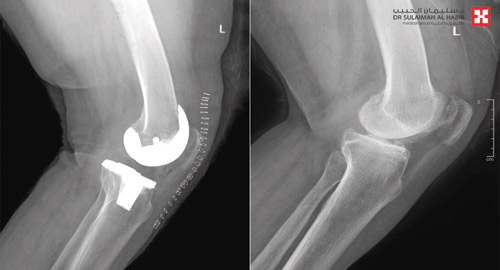

استعادت سيدة «ستينية» قدرتها على المشي، وتخلصت من الكرسي المتحرك، بعد ساعات من عملية نوعية لاستبدال مفصل ركبة، خضعت لها في مستشفى الدكتور سليمان الحبيب بالسويدي، بتقنية تخفف الآلام وتسرع التشافي، أنهت معاناتها مع الخشونة والاحتكاك الحاد وتلف غضاريف المفاصل، وغيرها من التبعات الحادة. وقال د. رغيد شبو استشاري جراحة العظام والإصابات واستبدال المفاصل، رئيس الفريق الطبي المعالج، أن المريضة حضرت إلى المستشفى وهي على كرسي متحرك تشكو من عدة أعراض، كالآلام المتزايدة والتورم وتغير شكل مفصل الركبة، بالإضافة إلى عدم الثبات عند محاولة تحمل الوزن، ورجح الفحص السريري المبدئي وجود احتكاك حاد في المفصل، وهذا ما أكدته الفحوصات التي أجريت لها حيث بينت وجود تآكل في عظمتى المفصل، وارتخاء شديد في أربطة الركبة الجانبية، وخلل في حركة عظمة رأس الركبة. وقاد قرر الفريق الطبي إجراء عملية لاستبدال المفصل، بآخر صناعي يتوافق مع معطيات التشخيص الطبي للحالة، وتم فيها استبدال مفصل الركبة بآخر صناعي خاص بمثل هذه الحالات، وتكللت العملية التي استمرت لنحو 120» دقيقة، ولله الحمد بالنجاح التام، وتمكنت المريضة من المشي على قدميها بعد ساعات من العملية.

وأوضح د. شبو أن التقنية التي استخدمت في العملية تحافظ على سلامة الكثير من الأنسجة، مما يجنب المرضى الصعوبات المتمثلة في الآلام الحادة بعد التدخل الجراحي، وأيضاً طول مدتي التنويم والعلاج الطبيعي والتأهيل.